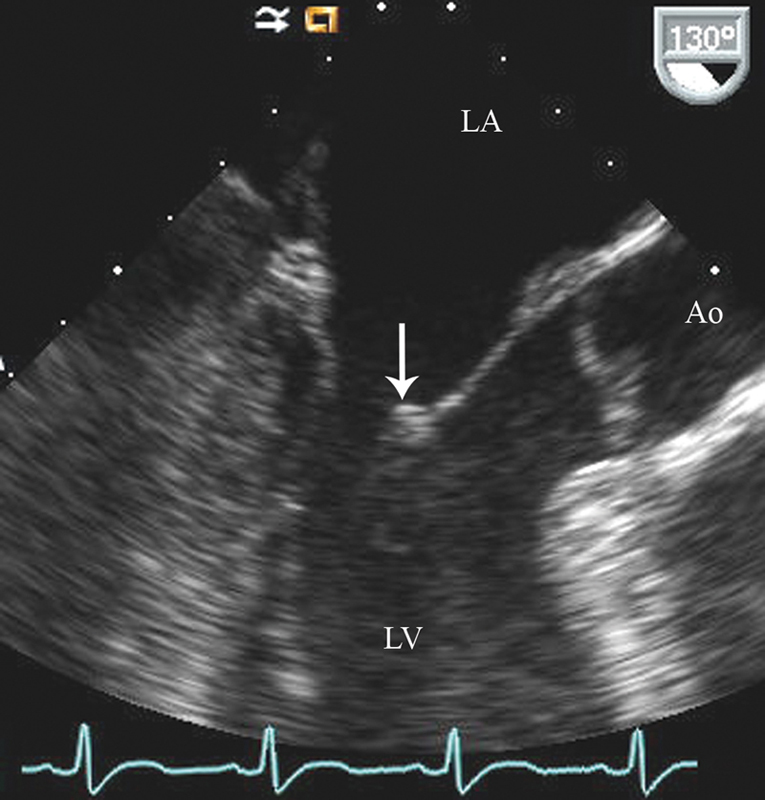

فحوصات تشخيصية لبعض امراض القلب والشرايين التاجية